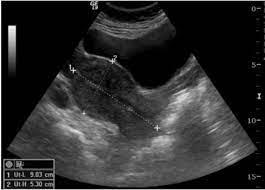

Japanese Society Of Sonographers

Japanese Society Of Sonographers from www.jss.org